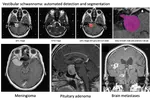

Recently, we organized a Public and Patient Involvement (PPI) group with Vestibular Schwannoma patients to understand their perspectives on an patient-centered automated report. Partnering with the British Acoustic Neuroma Association (BANA), we recruited participants by circulating a form within the BANA community through their social media platforms.

CAI4CAI members and alumni are leading the organization of the new edition of the cross-modality Domain Adaptation challenge (crossMoDA) for medical image segmentation Challenge, which will runs as an official challenge during the Medical Image Computing and Computer Assisted Interventions (MICCAI) 2023 conference.